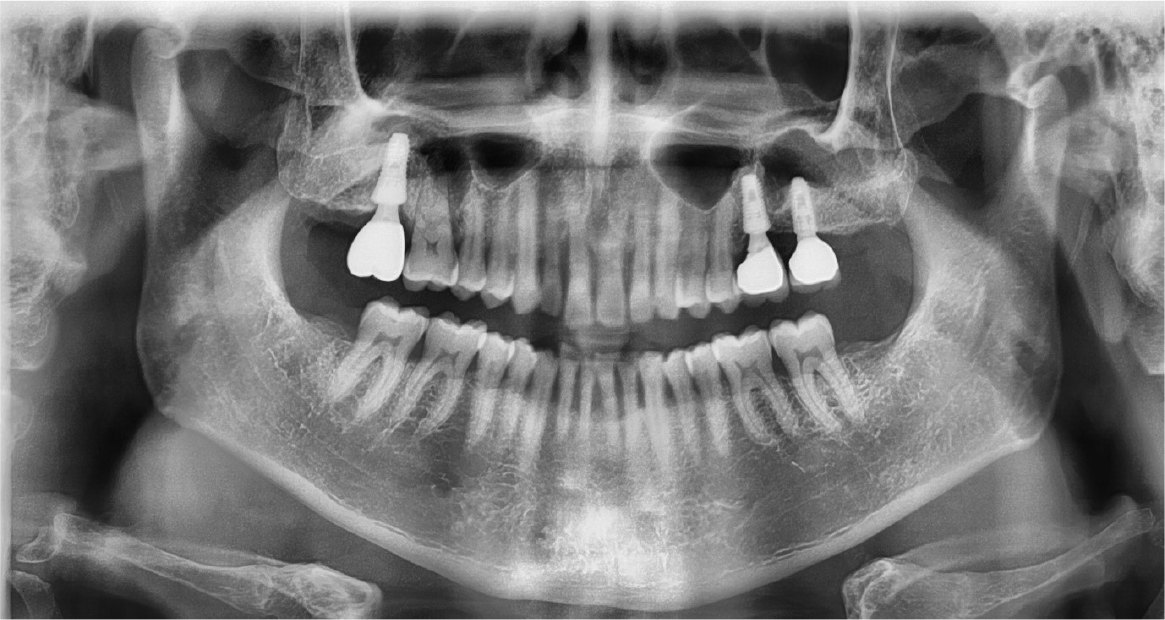

A 64-year-old man presented with a history of the severe pain and food packing of the right maxillary second molar. Clinical and radiological evaluation revealed a root caries of the right maxillary second molar (Fig. 1). The patient had the history of controlled hypertension and he was a heavy smoker (about 1 pack per a day). It was diagnosed with cemental caries on the right maxillary second molar and the immediate implant placement with sinus lift (window approach) was scheduled under local anesthesia because of gaining primary stability through inter-septal bone and the inferior wall of the sinus. Local anesthesia was carried out with 2% lidocaine containing 1:100,000 epinephrine (Huons Co., Seongnam, Korea). One vertical incision was made at mesial end of the horizontal incision.

The right maxillary second and third molars were extracted. A lateral bony window was prepared, and the sinus membrane was thoroughly lifted from the sinus floor with bony window lifted upward and inward. But the mesial aspect of the lifted sinus membrane was perforated (about 4 – 5 mm). A collagen wound dressing (Colla-tape®; Zimmer Dental Carlsbad, CA, USA) was used for the repair of the sinus membrane perforation (Fig. 2). Alloplastic bone-grafting material (A-oss®; Osstem implant Co., Seoul, Korea) was packed and the implant placement (Superline®; Dentium implant Co., Seoul, Korea) was performed (Fig. 3). After 7 days, the patient had pain, nasal discharge and foul odor on the right paranasal area. Under local anesthesia, the flap was elevated. The infected bone material, fixture, collagen wound dressing and infected tissue were removed (Fig. 4). Sinus irrigation was performed for about 5 minutes, until the foul odor and the blockage of ostium disappeared. During this procedure, the size of perforation got bigger by about 1 cm.